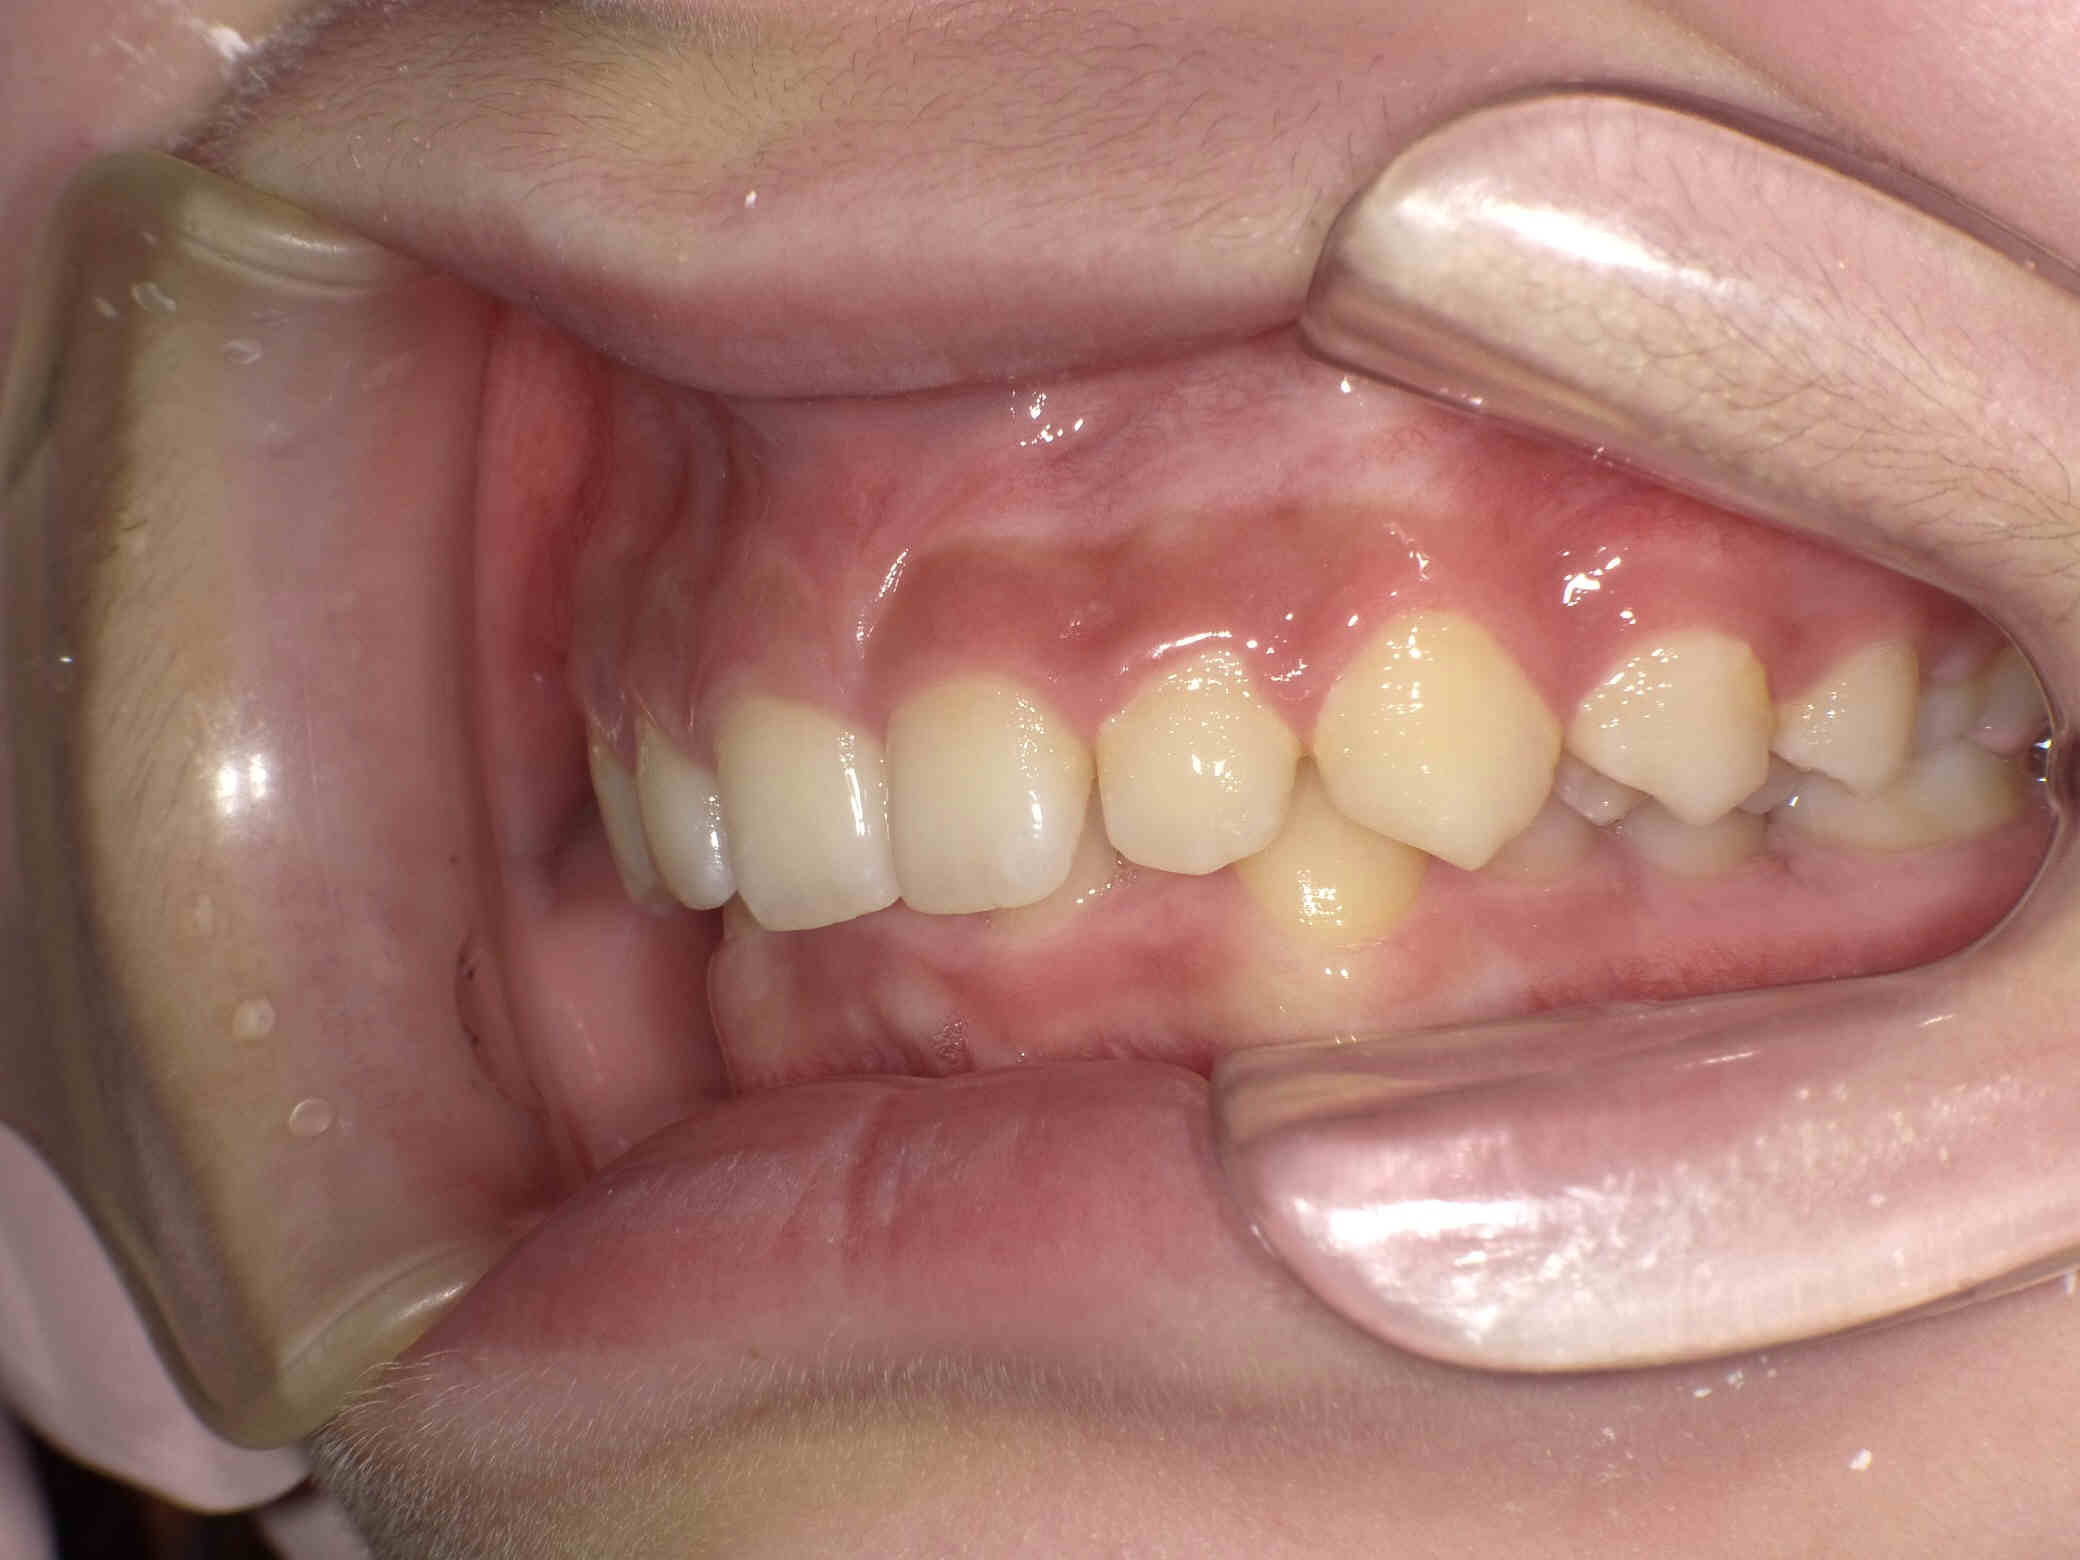

やや出っ歯傾向で、噛み合わせが深く

歯並びがデコボコな鋏上咬合(はさみじょうこうごう)という状況でした。

上下の歯がすれ違っている状態で、一部の歯に過度の負担がかかってしまいます。

今回はご希望のワイヤー矯正で治療を行い、スタートから1年半で美しい歯並びに改善しました。